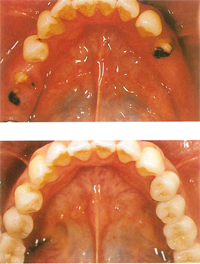

【歯がまったくない場合】

下顎の歯が1本も無い場合の修復にはインプラントがよく利用されます。

インプラントのヘッド部をバー状の維持装置で連結し、その上に取り外し式の入れ歯をしっかりと固定することができます。